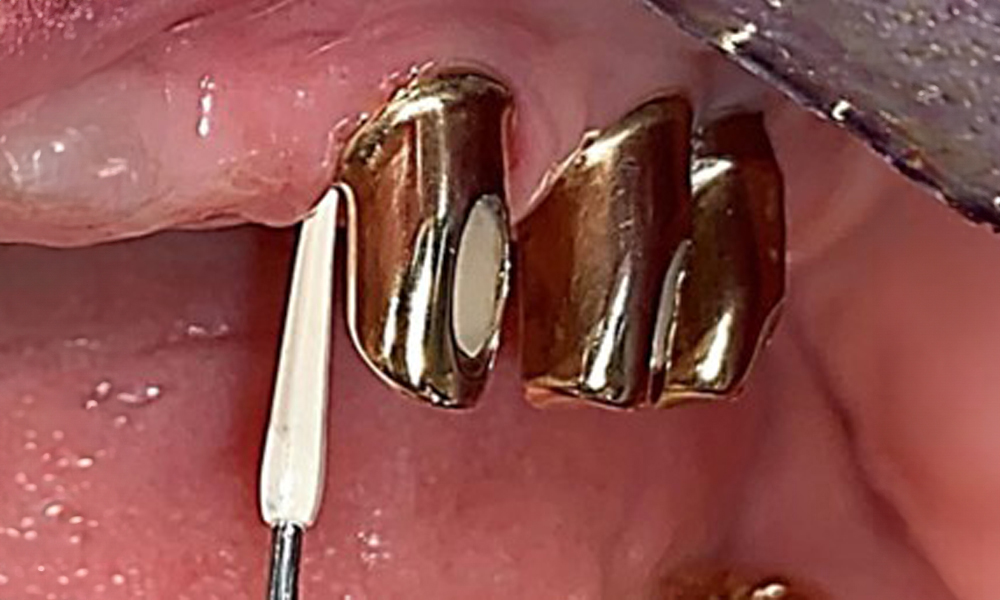

На пациентката е поставена комбинирана подвижна горночелюстна телескопична протеза преди повече от 25 години (фиг. 1, фиг. 2, фиг. 3) и тя е много доволна от протезите си. Пациентката има адекватна фиксирана протеза за долната челюст (фиг. 4).

Денталните открития са следните: Комбинирани снемаеми протези на импланти и телескопични протези, поддържани от зъби, на импланти 15, 13, 21, 23, 24, 25 и зъб 11 (фиг. 1, фиг. 2, фиг. 3). Пациентът е снабден с фиксирана долночелюстна протеза. Над зъби 37-34 и 45-47 бяха налични адекватни мостове (фиг. 4), краищата на коронките бяха интактни и нямаше активен кариес. Върху зъб 43 имаше композитна пломба с маргинална празнина. Имаше рецесия на долната гингива, която разкриваше от 1 до 3 mm от кореновата повърхност. Това се отнася и за 11.

Състоянието на пародонта остава стабилно. Няма възпаление на гингивата или периимплантатните меки тъкани. Дълбочините на сондиране от 1 до 3 mm бяха във физиологичния диапазон. Налице са генерализирани рецесии с размери от 1 до 3 mm. Имплант 23 е с увеличена дълбочина на сондиране от 4 mm, въпреки че няма признаци на секреция или кървене (фиг. 6). Общата стойност на BOP е 12 %.